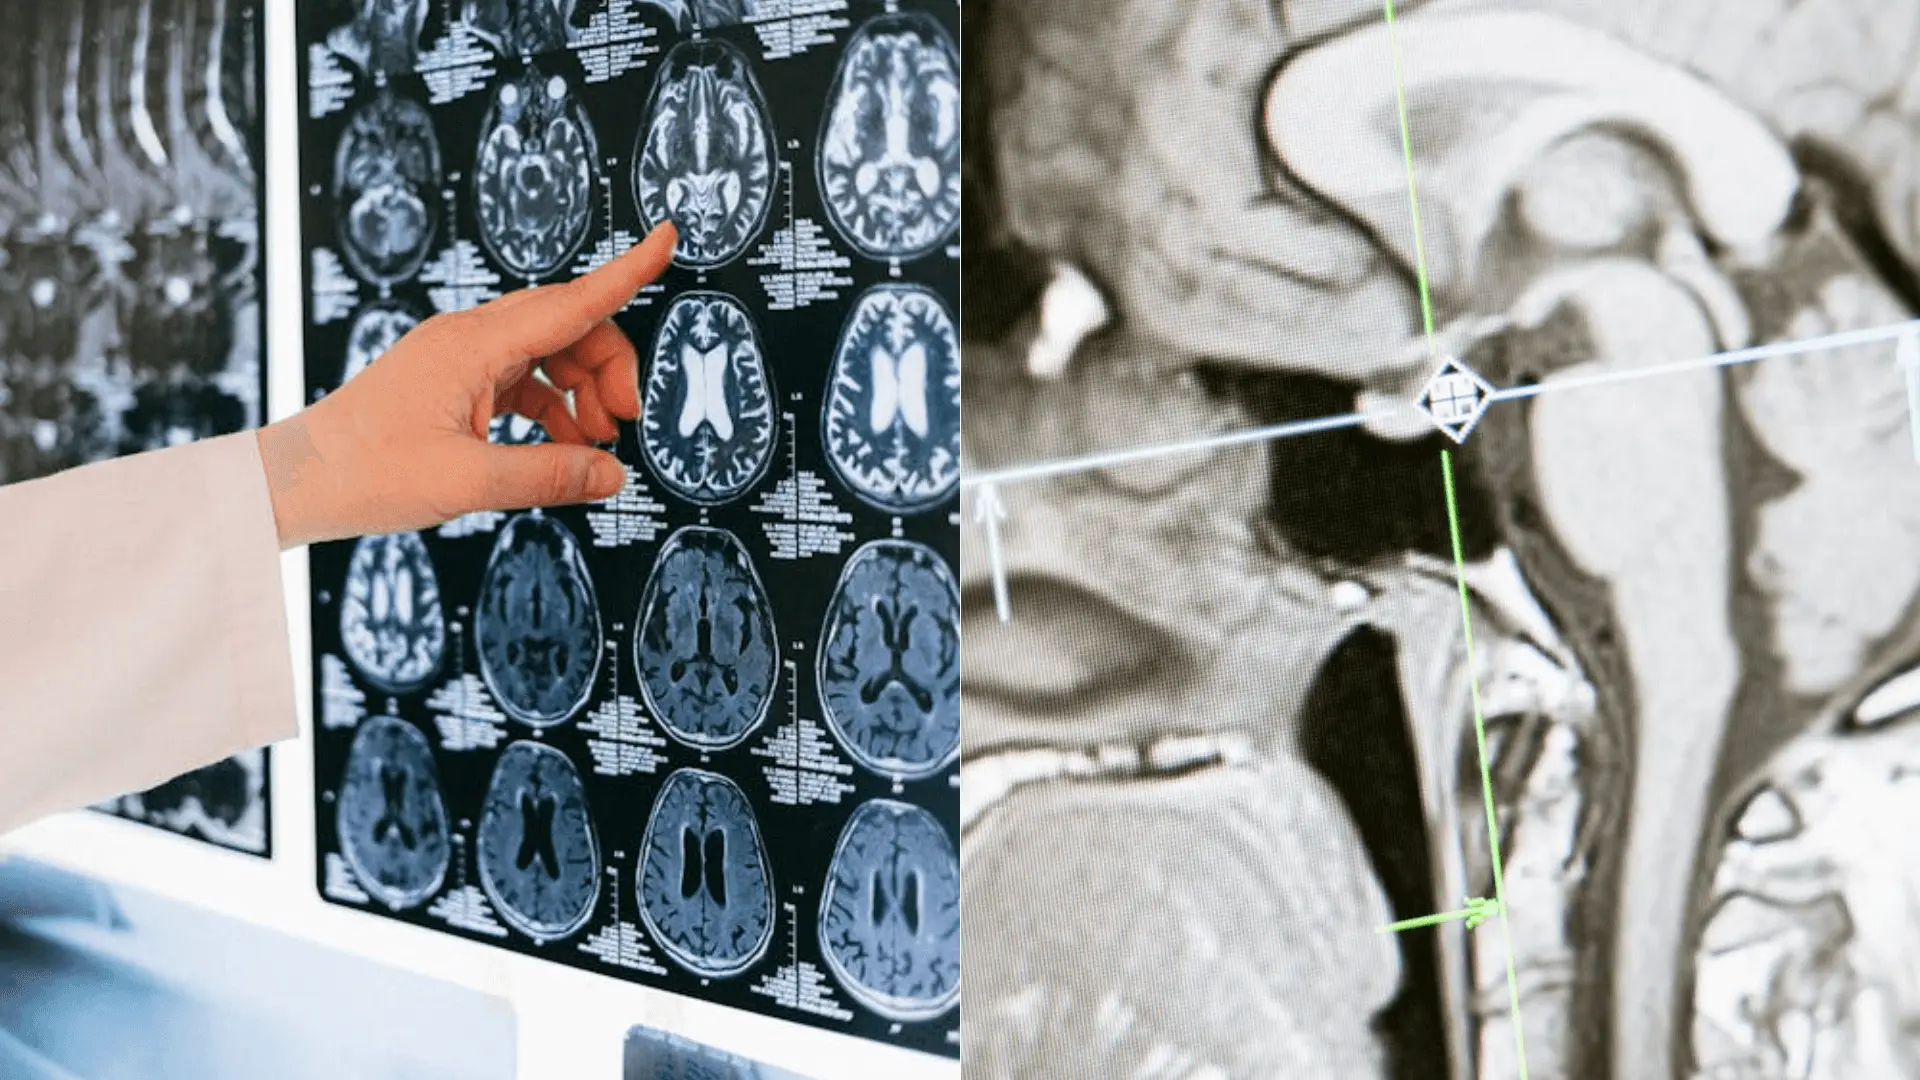

AI systém je navrhnutý na analýzu CT snímok mozgu pacientov s podozrením na mŕtvicu. Oproti tradičnému vizuálnemu hodnoteniu lekárov, ktoré sa spolieha na intenzitu tmavých oblastí na snímkach, je softvér schopný dosiahnuť dvojnásobnú presnosť. To je možné vďaka jeho schopnosti analyzovať textúru, variácie a biologický vek poškodených tkanív. Píše o tom imperial.ac.uk.

Softvér AI bol trénovaný na 800 snímkach mozgu, pri ktorých bol známy čas vzniku mŕtvice. Algoritmus automaticky identifikuje postihnuté oblasti na CT snímkach, analyzuje ich a určuje odhad času vzniku mŕtvice. Pri testovaní na takmer 2000 pacientoch preukázal dvojnásobnú presnosť oproti štandardnej metóde vizuálneho hodnotenia.